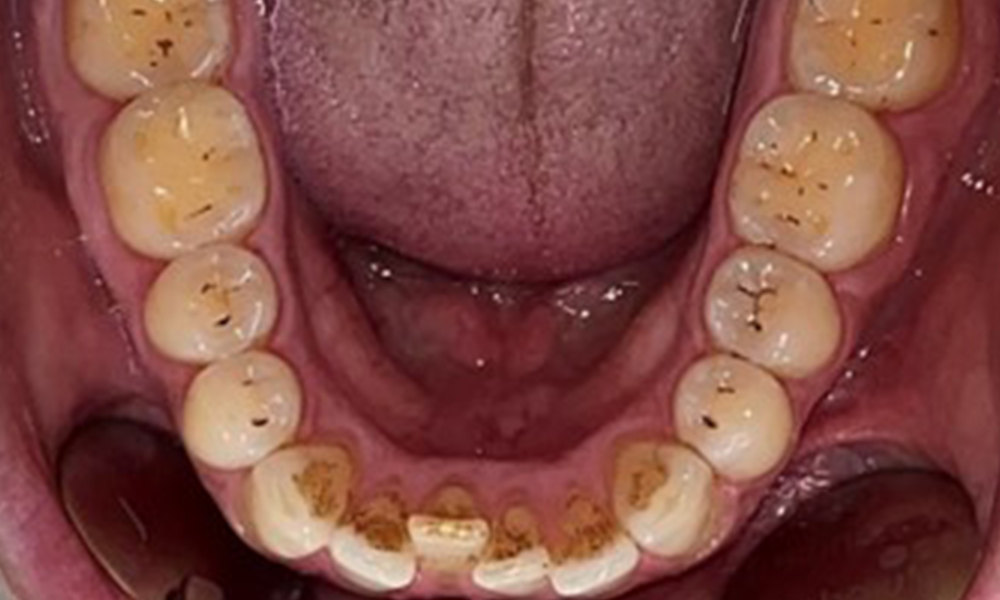

There were no pathological extraoral findings. During intraoral examination, inspection of the frontal view revealed brownish discolouration near the keratinised gingiva and at the transition to the moveable mucosa (Fig. 2), which could be attributed to nicotine consumption. Whitish mucosal lesions were observed on the palate, particularly near the maxillary molar palatal surfaces, indicating increased keratinisation and can also be attributed to nicotine consumption. The tongue was covered with a removable white and brownish coating.

The patient has full dentition with a total of 28 teeth. There were noteworthy erosions and attritions. (Fig. 4, Fig. 5). Due to bruxism, the patient has been wearing a splint with an adjusted bite block at night for many years. The erosions were caused by long-term consumption of isotonic beverages. No periodontal bone loss or active caries were observed.

Instruction and motivation are important components of these appointments. Good home-based intraoral hygiene behaviour and understanding are important for patients. Plaque accumulation is particularly evident in the cervical regions (Fig. 8).